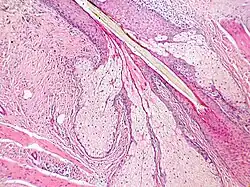

Tecido epitelial de revestimento

O tecido epitelial de revestimento possui peculiaridades que estão diretamente ligadas às suas funções. As células estão intimamente ligadas por meio dos complexos unitivos ou juncionais, há escassez de material intercelular (matriz extracelular) e há o que chamamos de polaridade celular (polo apical - aquele voltado para a luz do órgão e polo basal - aquele em contato com a membrana basal).

Como função do epitélio de revestimento podemos citar o órgão de impacto imediato do organismo, a pele, a qual possui o epitélio do tipo pavimentoso estratificado queratinizado, que impede a ação microbiológica patogênica conferindo proteção, evita o ressecamento do organismo e ameniza a ação de choques mecânicos. Está presente nos órgãos e é ele que recobre toda e qualquer cavidade (exemplo a cavidade gastrointestinal e respiratória).

O epitélio de revestimento pode ser classificado de acordo com o número de camadas: epitélio simples e epitélio estratificado e uma subclassificação o epitélio pseudo-estratificado. E quanto à sua forma: pavimentoso, cúbico e prismático, colunar ou cilíndrico. Epitélios simples possuem apenas uma camada de células. Epitélios estratificados contêm mais de uma camada de células. Epitélios pseudo-estratificados são assim chamados pois, embora sejam formados por apenas uma camada de células, os núcleos parecem estar em várias camadas. Todas as células estão apoiadas na lâmina basal, mas nem todas alcançam a superfície do epitélio, fazendo com que a posição dos núcleos seja variável.

O endotélio, que reveste os vasos sanguíneos e linfáticos, e o mesotélio, que reveste cavidades do corpo, como a cavidade pleural e peritoneal, e também recobre as vísceras, são exemplos de epitélios pavimentosos simples. Um exemplo de epitélio cúbico é o epitélio que reveste externamente o ovário, e um exemplo de epitélio prismático é o revestimento do intestino delgado. Um exemplo de epitélio pseudo-estratificado prismático ciliado é o que reveste as passagens respiratórias.[8]